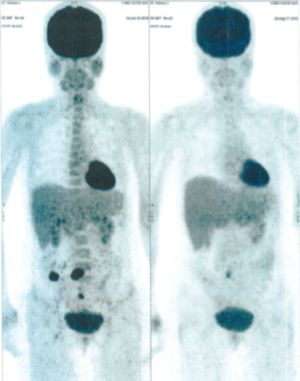

CASE NO: 6 (BREAST CANCER)

A middle-aged women treated for breast cancer now presents with massive liver metastases and a few bone metastases. She refused conventional chemotherapy and came to see us. After just 2 treatment, most of the cancer went into remission and those remaining are less active. Treatment will continue until complete remission.